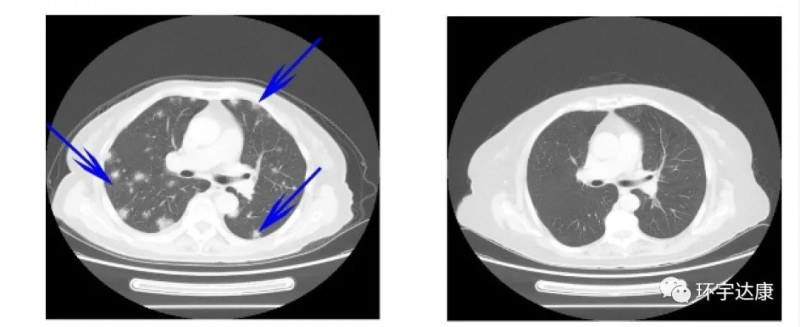

肺癌是发病率和死亡率最高的癌症,临床中需要更多的治疗方式。研究人员猜想非小细胞肺癌患者通过将TILs和抗PD-1疗法的组合,是否也能出现持久的完全缓解?在今年的AACR会议上,这一组合初步数据公布,非常鼓舞人心。这项试验是由美国知名癌症中心莫菲特癌症研究中心(H. Lee Moffitt )开展的,Ⅰ期临床结果公布:在12名可评估的非小细胞肺癌患者中,TIL疗法可达到25%的总缓解率,其中2名患者达到持久的完全缓解。值得振奋的是,大部分患者在接受TILs治疗后,肿瘤病灶都有所缩小,在接受治疗后的第一次CT扫描时,肿瘤病灶直径平均缩小38%!

其中一位晚期骨肉瘤患者已经出现了双肺转移,TIL加抗PD1治疗后12周后双肺多个转移(蓝色箭头)完全缓解。

这些结果表明,TILs疗法联合PD-1显着提高了转移性骨肉瘤患者的治疗效果。